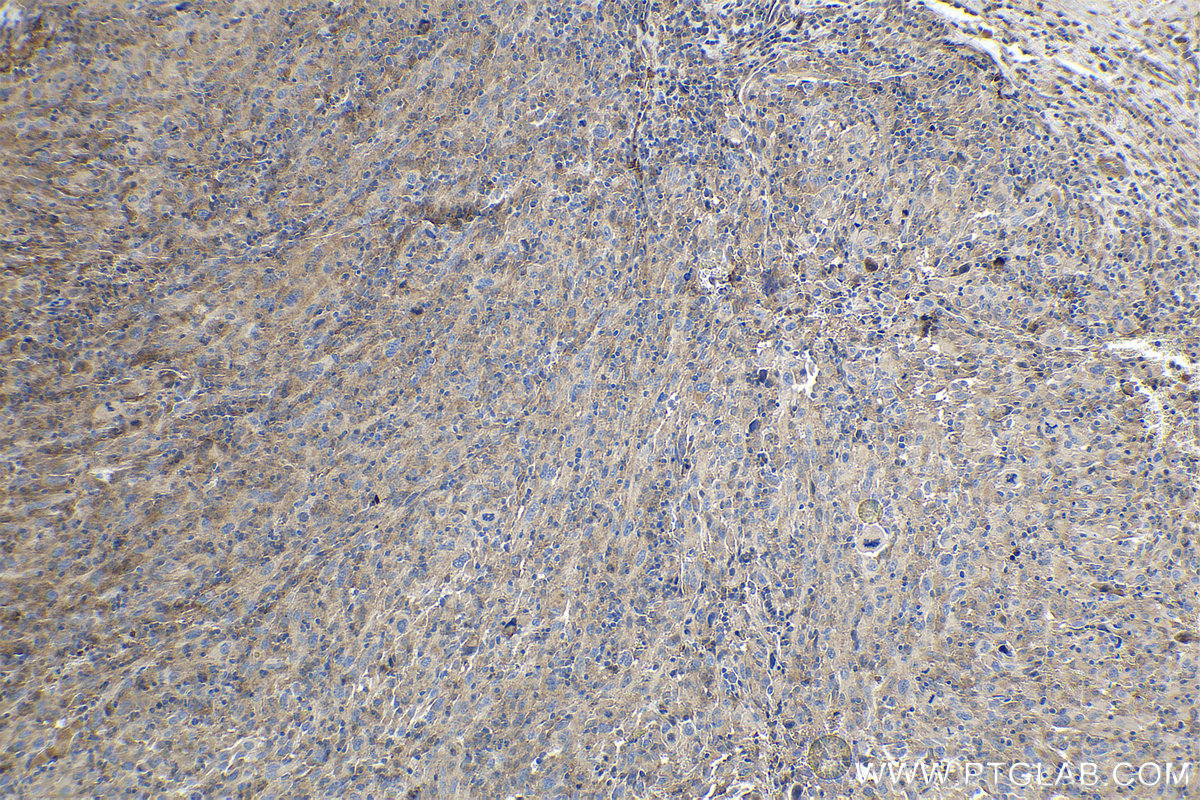

| Positive IHC detected in | human cervical cancer tissue, human skin cancer tissue Note: suggested antigen retrieval with TE buffer pH 9.0; (*) Alternatively, antigen retrieval may be performed with citrate buffer pH 6.0 |

| Immunohistochemistry (IHC) | IHC : 1:250-1:1000 |